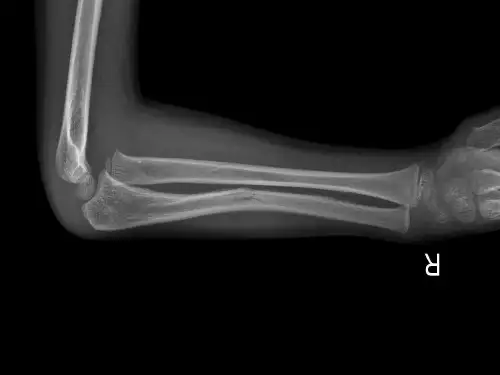

临床表现与诊断标准X线检查X线检查是诊断孟氏骨折的基础手段,可以显示骨折的类型、移位程度和关节脱位的情况。

常规拍摄包括肘关节正侧位片,必要时可加拍斜位片以排除交叉韧带损伤。

四、孟氏骨折的诊断孟氏骨折的诊断主要依据临床表现和X线检查。

此外,医生会安排X线检查以确定骨折的具体部位和类型。

通过详细的体检和X线检查,医生可确诊孟氏骨折。

其他特殊类型03孟氏骨折的诊断与鉴别诊断1诊断标准与依据23桡骨头、颈干、尺骨鹰嘴部骨折、尺骨近端向后移位。

典型表现显示桡骨头、颈干、尺骨鹰嘴部骨折及尺骨近端移位。